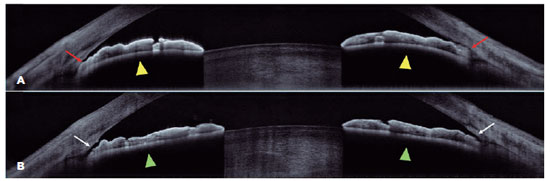

All images were exported to ImageJ® software (V.1.50i) and analyzed by an examiner blinded to gonioscopy results. Only images with clearly discernible scleral spur (SS) and correctly centered on a pupil at vertical and horizontal axes were analyzed. The SS was determined based on the point at which there was a change in the curvature in the corneoscleral aqueous interface, or in the apex of an internal projection of the inner margin of the cornea and trabecular meshwork, and the point at which the interface line between the less reflective ciliary muscle and sclera intersects with the inner corneal margin(12). After manually marking the SS, all quantitative variables were measured (Figure 1). The angle parameters evaluated were the angle opening distance at 250, 500, and 750 µm from the SS (AOD250, AOD500, and AOD750, respectively), trabecular-iris space at 500 µm from the SS (TISA500), trabecular-iris angle (TIA), trabecular-iris contact length (TICL) iris curvature (ICURVE), pupillary distance (PD), and lens vault. The definitions of each parameter were previously described(13). A quadrant was considered closed on AS-OCT if any contact between the iris and corneoscleral surface anterior to the scleral spur could be detected.

11-fig01tb.jpg)